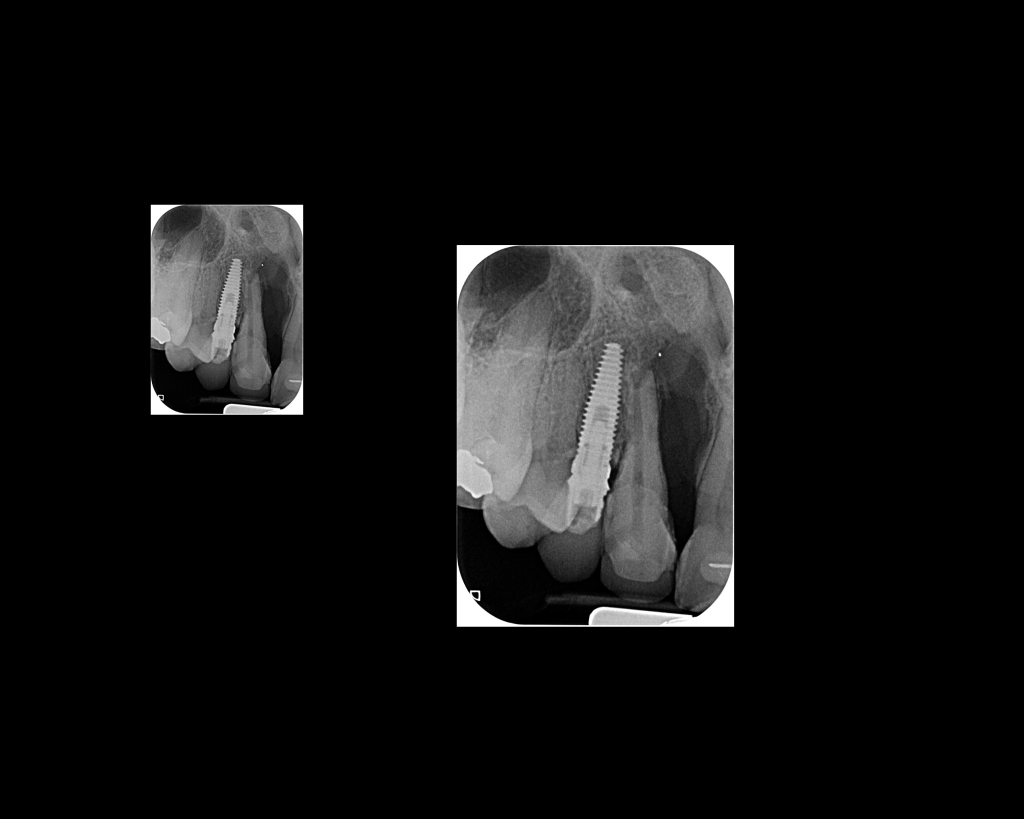

El Centro Radiológico Diagnóstico Oral 3D, es una empresa antioqueña que ofrece a sus pacientes desde el año 2009, tecnología de vanguardia en radiografías tridimensionales con calidad fotográfica. Las posibilidades para mejorar la eficacia en los diagnósticos bucales son evidentes, también lo son las posibilidades de manipulación de imagen. El sistema de imágenes en 3D ofrece detalles sin precedentes, convirtiéndola en la opción idónea para la mayoría de aplicaciones odontológicas, incluyendo implantes, tratamiento de conductos, ortodoncia, odontopediatría, periodoncia y cirugía

El mayor beneficiado con el uso de esta tecnología es el paciente, el cual podrá ser evaluado en todas sus dimensiones con una baja dosis de radiación, con un costo accesible y sin contaminar  el medio ambiente. Dependiendo de la necesidad del paciente, hay varios tipos de tomografías y los especialistas en el área odontológica hacen uso de ellas según su especialidad.

Evaluación de patologías dentales y maxilofaciales

Implantología dental

Diagnóstico de traumatismos dentales y maxilofaciales